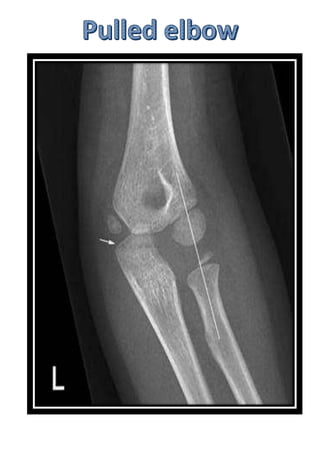

Multiple healing fractures

Female>male

50% cases bilateral

Defect- distal end of the radius growth

plate fuses early

Defect in growth (but ulna continues to

grow normally)

Deformity:

Ulna is more prominent than the radius.

Volar subluxation of hand – dinner fork

deformity